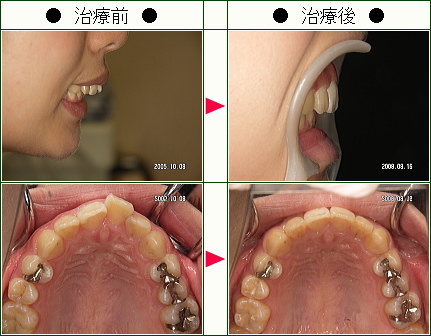

☆歯のデコボコ矯正症例(甲斐様 38歳 女性)